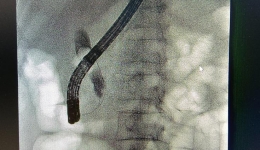

不开刀,胆管结石嘴里取——内镜技术ERCP

近日一位患者,突发腹痛、寒战高热的患者到茂名市人民医院消化内一科就诊。消化内科吴振华主任为患者完善相关检查,结果发现患者胆总管多发结石,且出现梗阻性黄疸。刻不容缓,消化内科吴振华主任团队马上为进行手术,手术过程顺利。目前,患者已康...